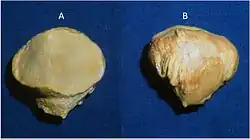

Manchmal macht die röntgenologische Abgrenzung der Patellafraktur von einer Patella partita (lat.: zweigeteilte Kniescheibe), also einer während der Entwicklung ausgebliebenen Verschmelzung der Knochenkerne, diagnostische Schwierigkeiten. Während sich frische Frakturen scharfkantig abbilden, findet man bei der Patella partita abgerundete Kanten, die „Fragmente“ sind nicht miteinander kongruent. Auch fehlt bei der Patella partita in der Regel der typische klinische Befund einer Patellafraktur, es besteht keinerlei Funktionsverlust. Wichtig ist die Unterscheidung für die Indikation zur Operation: Nur die frische Fraktur profitiert von der OP.

Differentialdiagnose Patella bipartita: Im Gegensatz zur Längsfraktur (s. unten) abgerundete Kanten der Fragmente

Differentialdiagnose Patella bipartita: Im Gegensatz zur Längsfraktur (s. unten) abgerundete Kanten der Fragmente -